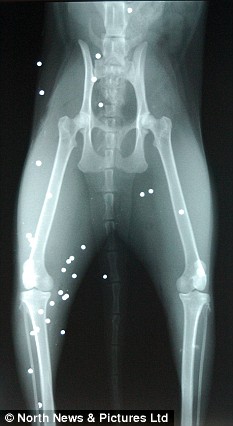

X光顯示羅西的身體里嵌入多達50枚子彈

兩歲的貓咪羅西11日遭到了一幫社會氓流的襲擊。等到主人特蕾西發(fā)現(xiàn)它的時候,這個可憐的小家伙正倒在血泊中,努力拖動被打瘸的后腿并痛苦地哀嚎著?!拔耶敃r驚呆了,它渾身都是血,”特蕾西說?!傲_西一共有大約50處傷口,獸醫(yī)取出了其中20枚子彈,剩下的30枚將永遠嵌入它的身體。我太憤怒了,簡直不能相信有人竟然如此殘忍地對待小動物?!?/p>

獸醫(yī)特納表示:“這是我第一次救治一只被子彈擊中的貓。50枚子彈對于貓而言實在太多了,可它十分幸運?!?/p>